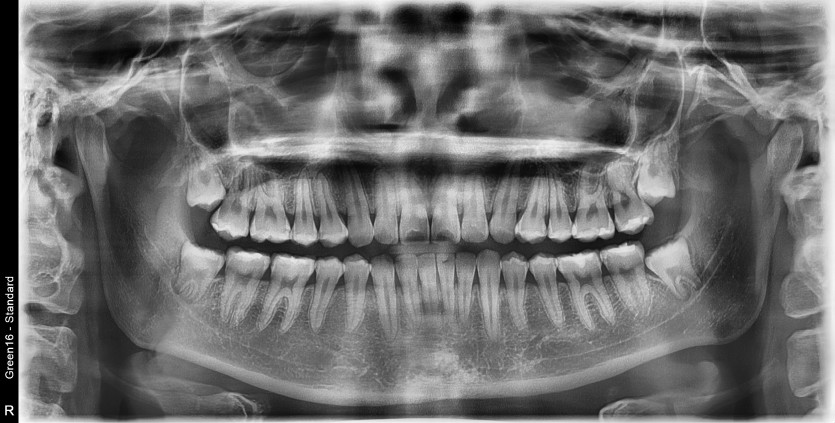

#48 사랑니 발치

구강 외과 전문의가 당일 발치했습니다.